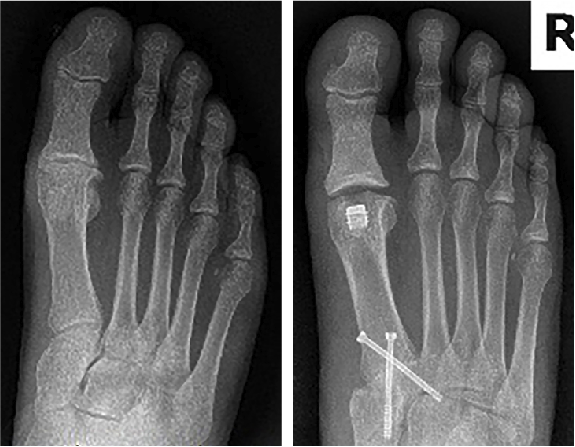

Previous right foot X-ray findings included long and elevated first metatarsal with a large osteochondral defect of the central metatarsal head with eburnation and dorsal spurring consistent with moderate-to-severe primary osteoarthritis of the great toe joint (Stage 3 Coughlin and Shurnas classification).

Twelve-week X-rays revealed continued full consolidation of his first metatarsal-internal cuneiform arthrodesis, which allowed shortening and plantarflexing of the first ray. Joint space was increased in the first MTPJ with adequate bone removal noted. There was no implant subsidence or ectopic bone formation, the implant was stationary, and no movement evident. The patient was very pleased with the procedure and had very minimal swelling of his right foot at 12 weeks postop with a pain level is 2/10.

At 4 months postop we performed hardware removal (two 3.0-mm partially threaded cannulated cancellous screws) due to localized pain of the right midfoot only. Resolution of right midfoot pain occurred 2 weeks after this latest procedure.